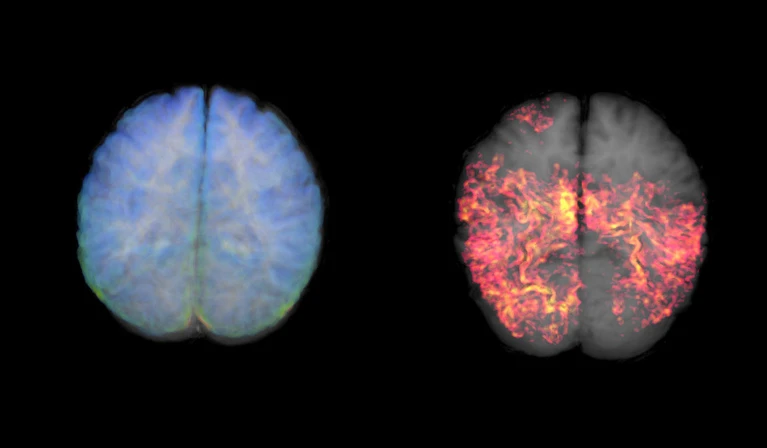

Bệnh Alzheimer được hình thành bởi sự tích tụ của các mảng bám amyloid-β và các đám rối protein Tau trong mô não. Cả hai loại protein này đều phá vỡ chức năng não, khiến các nơ-ron thần kinh chết dần, từ đó gây ra sự suy giảm nhận thức.